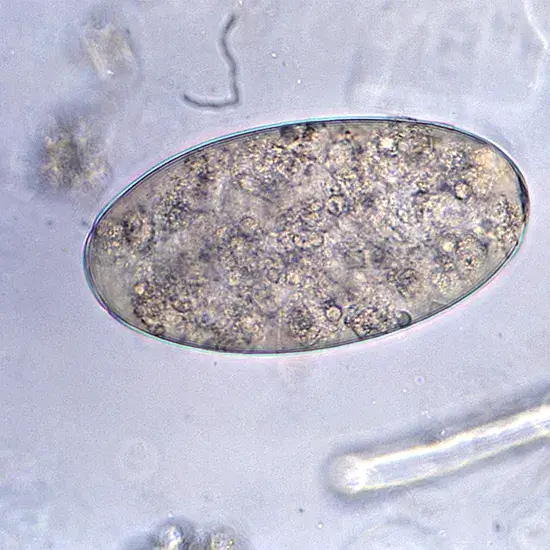

Fasciolopsiasis, also known as intestinal fluke infection, is a parasitic disease caused by the trematode flatworm Fasciolopsis buski. This parasite primarily infects the small intestine of humans and other mammals, and can cause a range of symptoms and complications.

Diagnosis of fasciolopsiasis is typically based on clinical evaluation, history of exposure to contaminated water or plants, and laboratory tests. These may include stool examinations to detect fluke eggs or adult flukes, imaging studies (such as ultrasound or CT scan) to visualize the intestine, and blood tests to detect specific antibodies or antigens.